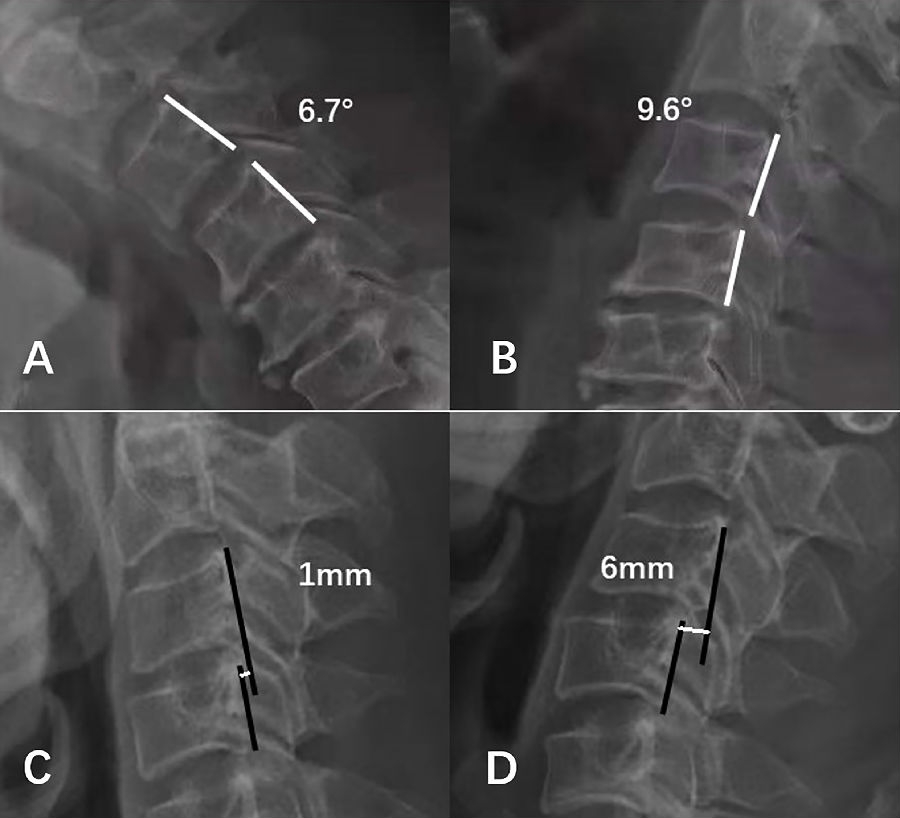

依据White等提出的标准,定义超过3.5mm水平位移或大于11°节段活动度为颈椎节段失稳(图5)。

图5.颈椎节段失稳示意图。A、B:角度失稳,节段活动度16.3°;C、D:位移失稳,节段位移5mm